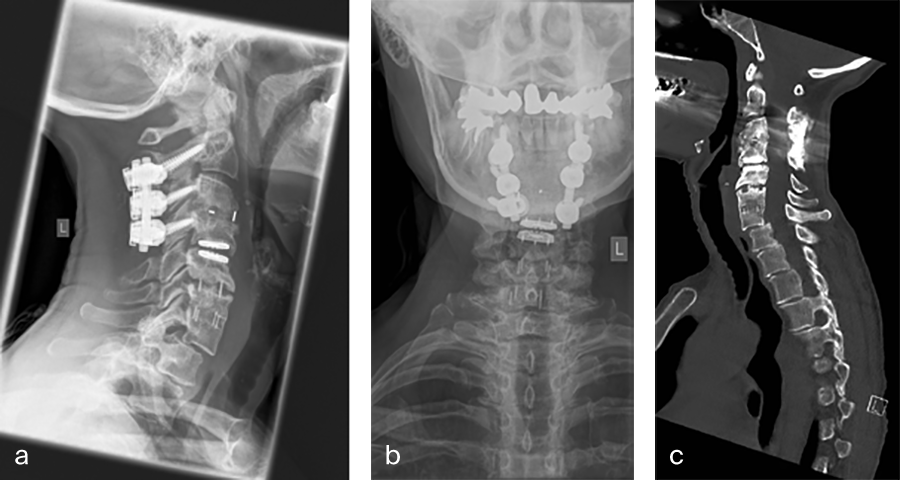

Her preoperative radiographic evaluation comprised two standard plane radiographs, functional radiographs, computed tomographic and magnetic resonance imaging scans (Fig 2) demonstrated:

- A fusion of the motion segments C2/3/4 and C6/7

- A moderate implant loosening of the posterior C2 screw on the right side

- An afunctional disc prosthesis at the level C4/C5 with significant heterotopic ossifications (grade III) accompanied by a facet joint osteoarthritis in this motion segment

- A nonunion at the level C5/C6 with residual mobility in this motion segment

- A highly mobile degenerative spondylolisthesis at the level C7/Th1 with bilateral neuroforaminal stenosis

Fig 2a–f Preoperative imaging showing: C2-C4 posterior instrumentation and fusion, anterior fusion after anterior cervical decompression and fusion (ACDF) C3/4 and C6/7, status after total disc replacement of C4/5 with heterotopic ossifications, nonunion C5/6 after ACDF C5/6, spondylolisthesis C7/Th1 with neuroforaminal stenosis on both sides and a normal cervical angiogram (cave: artefacts).